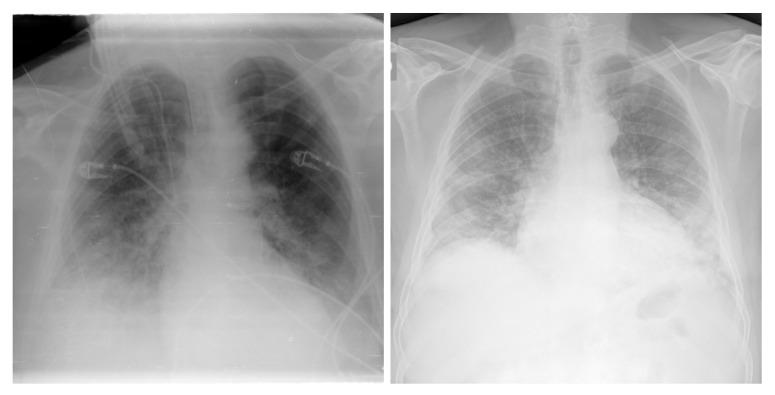

COVID-19,which is caused by the severe acute respiratory syndrome coronavirus 2 (SARS-CoV-2), is one of the worst pandemics in recent history. The identification of patients suspected to be infected with COVID-19 is becoming crucial to reduce its spread. We aimed to validate and test a deep learning model to detect COVID-19 based on chest X-rays. The recent deep convolutional neural network (CNN) RegNetX032 was adapted for detecting COVID-19 from chest X-ray (CXR) images using polymerase chain reaction (RT-PCR) as a reference. The model was customized and trained on five datasets containing more than 15,000 CXR images (including 4148COVID-19-positive cases) and then tested on 321 images (150 COVID-19-positive) from Montfort Hospital. Twenty percent of the data from the five datasets were used as validation data for hyperparameter optimization. Each CXR image was processed by the model to detect COVID-19. Multi-binary classifications were proposed, such as: COVID-19 vs. normal, COVID-19 + pneumonia vs. normal, and pneumonia vs. normal. The performance results were based on the area under the curve (AUC), sensitivity, and specificity. In addition, an explainability model was developed that demonstrated the high performance and high generalization degree of the proposed model in detecting and highlighting the signs of the disease. The fine-tuned RegNetX032 model achieved an overall accuracy score of 96.0%, with an AUC score of 99.1%. The model showed a superior sensitivity of 98.0% in detecting signs from CXR images of COVID-19 patients, and a specificity of 93.0% in detecting healthy CXR images. A second scenario compared COVID-19 + pneumonia vs. normal (healthy X-ray) patients. The model achieved an overall score of 99.1% (AUC) with a sensitivity of 96.0% and specificity of 93.0% on the Montfort dataset. For the validation set, the model achieved an average accuracy of 98.6%, an AUC score of 98.0%, a sensitivity of 98.0%, and a specificity of 96.0% for detection (COVID-19 patients vs. healthy patients). The second scenario compared COVID-19 + pneumonia vs. normal patients. The model achieved an overall score of 98.8% (AUC) with a sensitivity of 97.0% and a specificity of 96.0%. This robust deep learning model demonstrated excellent performance in detecting COVID-19 from chest X-rays. This model could be used to automate the detection of COVID-19 and improve decision making for patient triage and isolation in hospital settings. This could also be used as a complementary aid for radiologists or clinicians when differentiating to make smart decisions.

COVID-19 是由严重急性呼吸综合征冠状病毒 2(SARS-CoV-2)引起的,是最近历史上最严重的大流行之一。识别疑似感染 COVID-19 的患者对于减少其传播至关重要。我们旨在验证和测试一种基于胸部 X 光片检测 COVID-19 的深度学习模型。最近的深度卷积神经网络(CNN)RegNetX032 经过适应,可使用聚合酶链反应(RT-PCR)作为参考,从胸部 X 光(CXR)图像中检测 COVID-19。该模型在包含超过 15000 张 CXR 图像(包括 4148 例 COVID-19 阳性病例)的五个数据集上进行了定制和训练,然后在蒙福特医院的 321 张图像(150 例 COVID-19 阳性病例)上进行了测试。五个数据集的 20%的数据用于超参数优化的验证数据。模型处理每张 CXR 图像以检测 COVID-19。提出了多二进制分类,例如:COVID-19 与正常,COVID-19+肺炎与正常,肺炎与正常。性能结果基于曲线下面积(AUC)、敏感性和特异性。此外,还开发了一个可解释性模型,该模型证明了所提出的模型在检测和突出疾病迹象方面具有出色的性能和高度的泛化能力。经过微调的 RegNetX032 模型的整体准确率达到 96.0%,AUC 评分为 99.1%。该模型在检测 COVID-19 患者的 CXR 图像中的迹象方面表现出优越的敏感性,达到 98.0%,在检测健康 CXR 图像方面具有 93.0%的特异性。第二个场景比较了 COVID-19+肺炎与正常(健康 X 射线)患者。该模型在蒙福特数据集上的总体评分为 99.1%(AUC),具有 96.0%的敏感性和 93.0%的特异性。对于验证集,该模型的平均准确率为 98.6%,AUC 评分为 98.0%,敏感性为 98.0%,特异性为 96.0%用于检测(COVID-19 患者与健康患者)。第二个场景比较了 COVID-19+肺炎与正常患者。该模型的总体评分为 98.8%(AUC),敏感性为 97.0%,特异性为 96.0%。该强大的深度学习模型在从胸部 X 光片中检测 COVID-19 方面表现出出色的性能。该模型可用于自动检测 COVID-19,并提高医院环境中患者分诊和隔离的决策能力。当进行区分以做出明智决策时,它也可以作为放射科医生或临床医生的辅助工具。